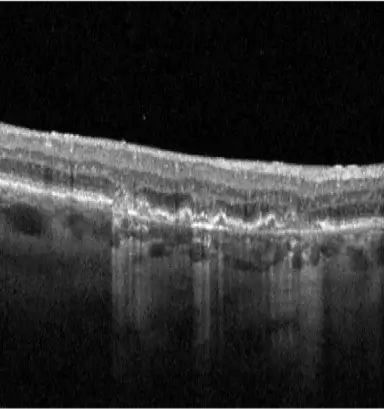

IZERVAY™ (avacincaptad pegol intravitreal solution) is indicated for the treatment of geographic atrophy (GA) secondary to age-related macular degeneration (AMD)